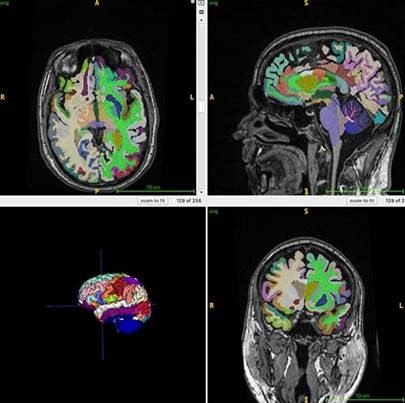

Метод: всем сделали МРТ тела и мозга и с помощью ИИ изучили количество мышц, внутреннего (висцерального) и подкожного жира.

Цель: определить биологический возраст мозга.